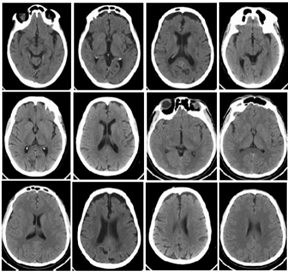

3. Data Acquisition

Figure 1. PCT slices